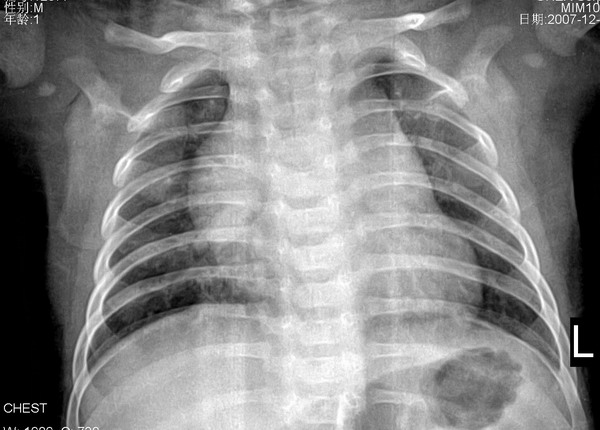

小儿肺1 仰卧前后位, 男110天,咳嗽2天,夜间尤甚,心脏听诊断无异常, 老师们给个意见!纵隔?

胸腺增大

小儿新影正常,有气肿改变纹理重,小儿肺炎.

支气管肺炎

加照侧位片,,先考虑胸腺增大.

先考虑胸腺增大.心肺膈未见明显异常。

纵隔增宽是胸腺影,心脏建议彩超

正常胸腺

正常。仰卧位纵隔心影都增宽

小儿正常胸腺似胸腺肥大。

考虑胸腺增大。建议心超检查。

支持胸腺肥大所致。

不太像增大的胸腺,支气管肺炎诊断请结合临床病史。

支气管肺炎----纹理增重,双下肺可见小斑状增密影。

有心缘改变首先考虑为胸腺所致,考虑支气管肺炎